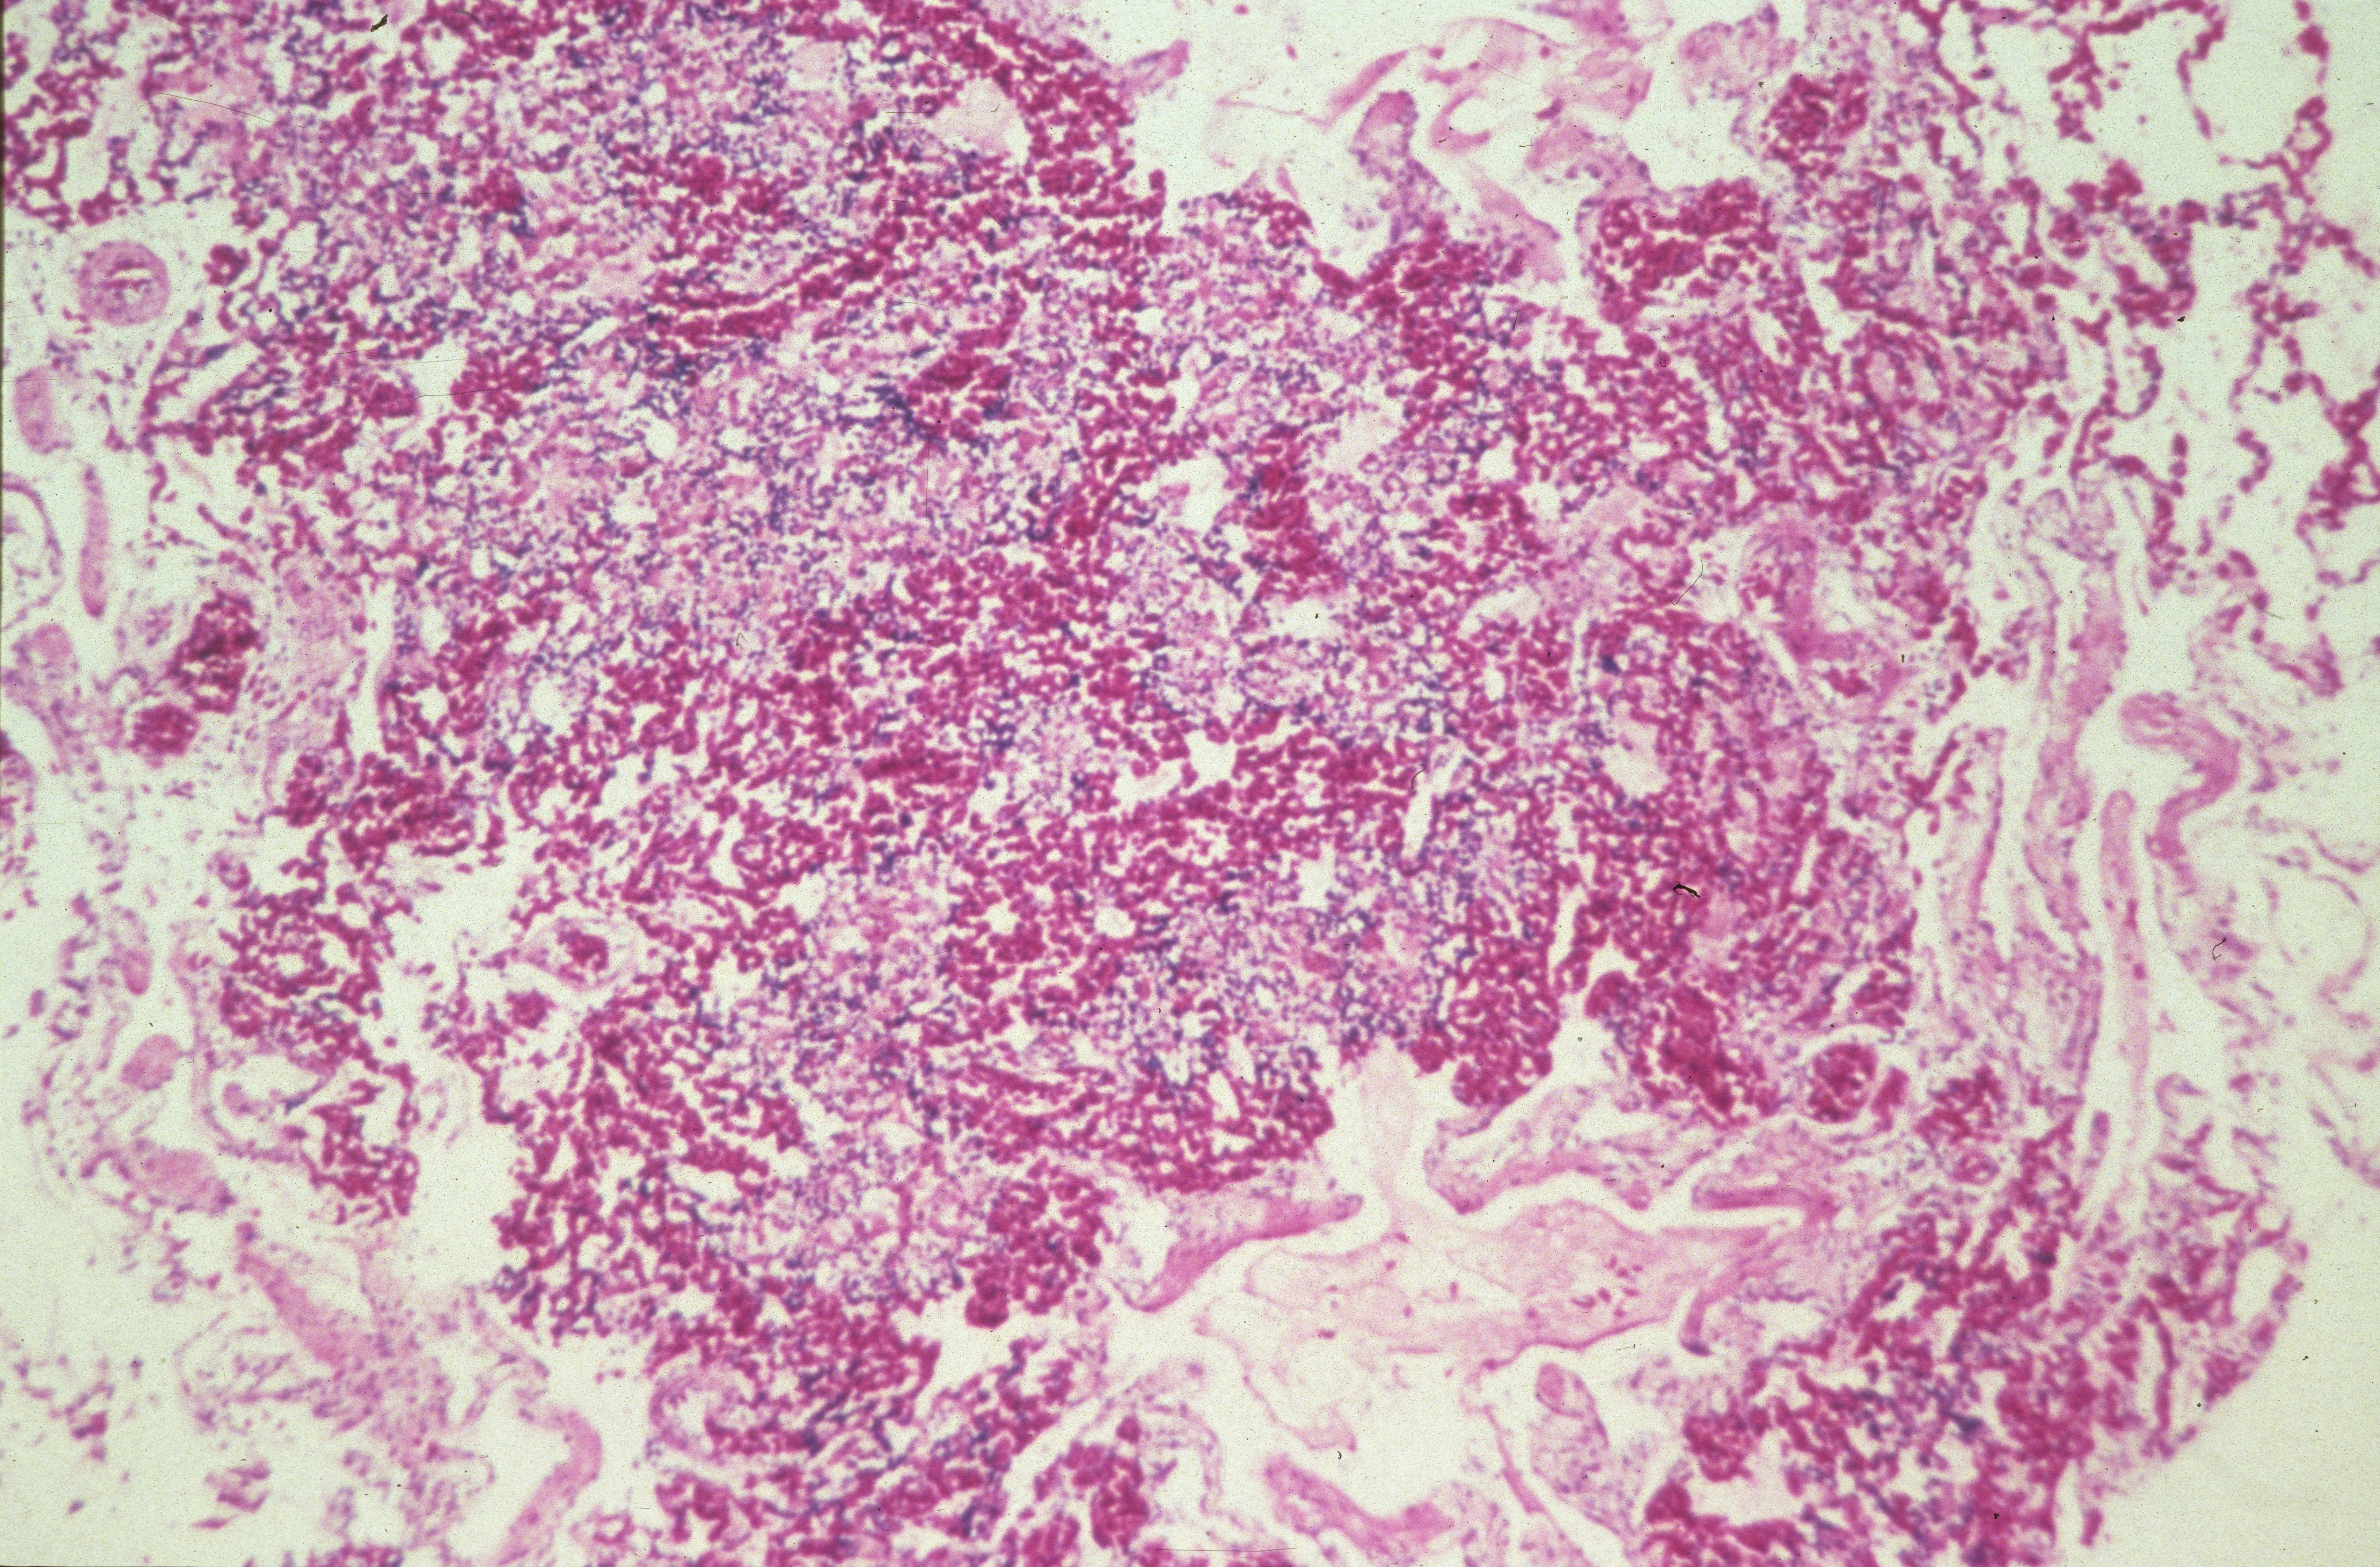

Marble spleen disease of ring-necked pheasants (slide study set no. 17) Item Info

Marble spleen disease of ring-necked pheasants (slide study set no. 17)

Slide study set #17, marble spleen disease of ring-necked pheasants, 2 sets (includes 40 color slides), undated